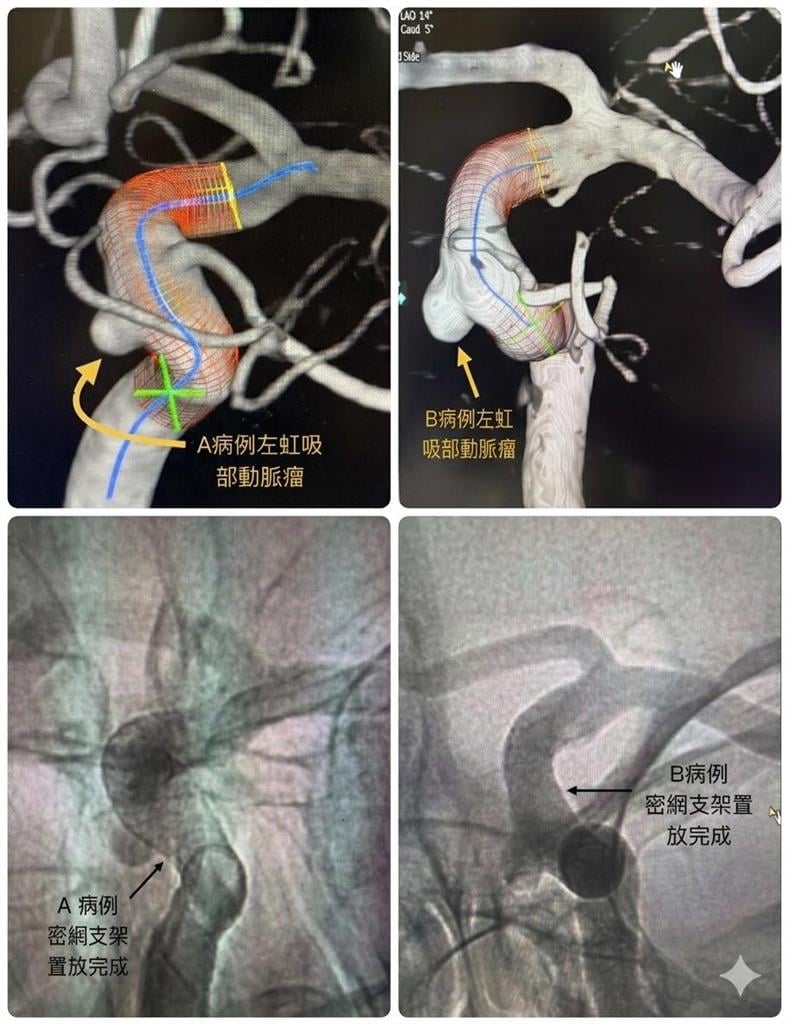

生活中心/張予柔報導一起看似離奇的醫療案例,近日在醫界引發關注。聯新國際醫院神經醫學中心執行院長陳啟仁分享,兩名年近50歲的男性友人,因為出現「頭脹脹的」不適感,分別前往檢查,沒想到竟在腦部相同位置發現動脈瘤,更巧的是,兩人過去曾在同一間公司任職,而他們的前老闆也疑似因動脈瘤破裂40多歲時猝逝,巧合程度讓人震驚。

一起看似離奇的醫療案例,近日在醫界引發關注。聯新國際醫院神經醫學中心執行院長陳啟仁分享,兩名年近50歲的男性友人,因為出現「頭脹脹的」不適感,分別前往檢查,沒想到竟在腦部相同位置發現動脈瘤,更巧的是,兩人過去曾在同一間公司任職,而他們的前老闆也疑似因動脈瘤破裂40多歲時猝逝,巧合程度讓人震驚。